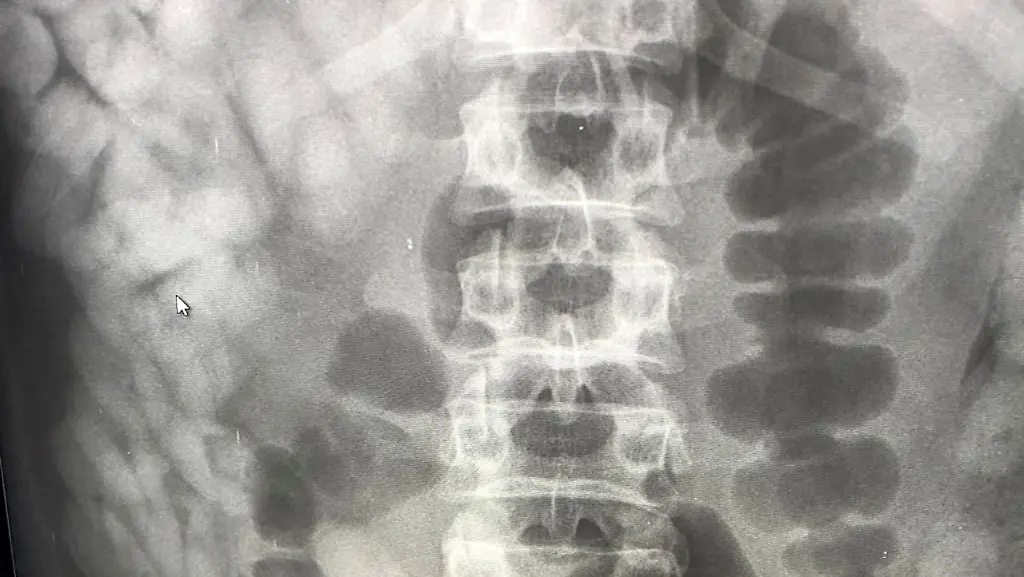

Da die Zöllner keine Drogen fanden, wurde der Mann im Krankenhaus geröntgt. "Das Röntgenbild bestätigte den Verdacht der Zöllner", sagte eine Sprecherin des Hauptzollamts München. "Im Laufe des Tages kamen 97 Behältnisse mit Kokain zum Vorschein, die über den natürlichen Weg ausgeschieden wurden." Der Schmuggler war aus Brasilien gekommen und wollte über München nach Spanien reisen. Gegen den Mann wurde Haftbefehl erlassen.